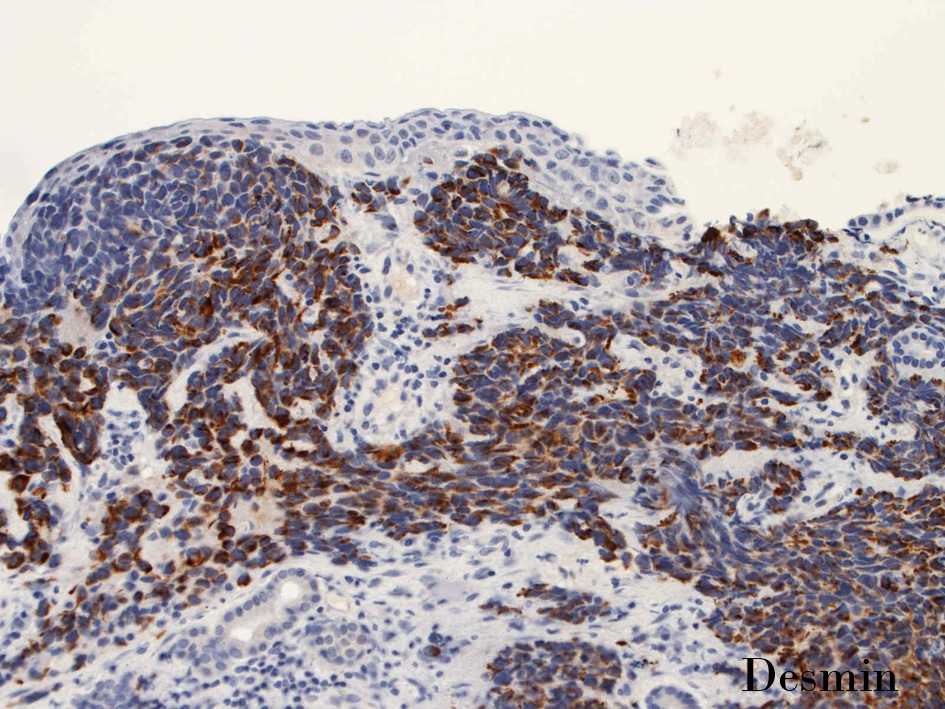

Desmin.jpg

Desmin_02.jpg

DesminDesminmyogenin

small round cell tumorの中でrhabdomyosarcomaは腫瘍細胞に種々の抗原が陽性となるため診断を誤ることがあり注意が必要である*1